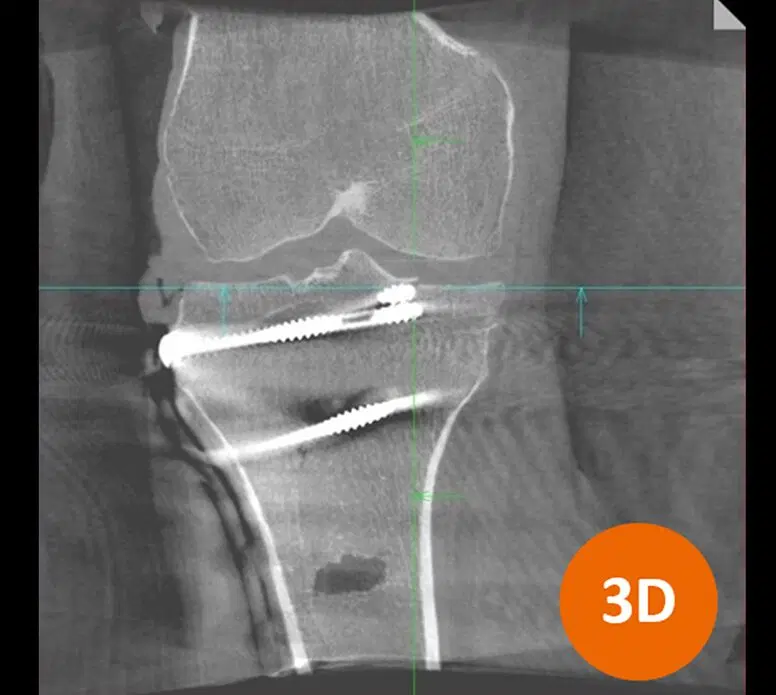

Estudios recientes han demostrado que entre el 20% y 40% de las cirugías de columna que parecerían satisfactorias al evaluarse en tecnología 2D, en realidad requerían correcciones que sólo podían detectarse mediante imagenología 3D.

En este contexto, el doctor Cristiano Menezes, especialista en cirugía ortopédica y referente en Latinoamérica, destacó cómo la tecnología de imagenología 3D intraoperatoria ha revolucionado su práctica clínica, al permitir una mayor precisión quirúrgica, reducir los riesgos para los pacientes y elevar los estándares de calidad en los procedimientos.

“Con la adquisición de este tipo de tecnología, el cirujano tiene la visualización inmediata de los implantes, que permite saber qué tipo de corrección es necesaria. A su vez esto garantiza y mejora las posibilidades de hacer cirugías más seguras y disminuimos la posibilidad de hacer más operaciones”, explicó el doctor Menezes.

La adopción de la imagen 3D intraoperatoria impacta directamente en la seguridad del paciente y en la eficiencia del sistema de salud. Al evitar reintervenciones, se disminuyen los riesgos de complicaciones asociadas a una segunda anestesia, infecciones, dolor postoperatorio y deterioro funcional.

El doctor Menezes afirmó que “Cios Spin, es un equipo de imagenología 3D que integra tecnologías avanzadas de radiología y robótica, lo que resulta esencial en fracturas de zonas complejas como el calcáneo, la pelvis o la cabeza femoral, donde errores milimétricos pueden afectar la movilidad o generar dolor crónico”.